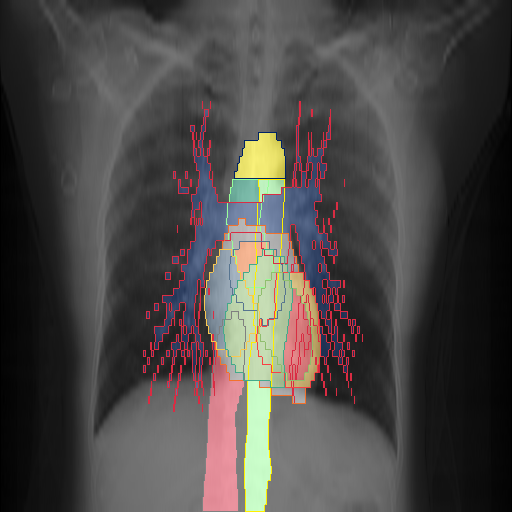

We show qualitative results for frontal projections in Fig. 2. We show a subset of classes belonging to the supercategories lungs, vascular systems, bones, and abdomen/digestive system. The predictions show minor deviations at the boundaries of the individual classes of the respiratory and vasculature system, while some inaccuracies become visible in the abdominal area. The qualitative results for the lateral projections are displayed in Fig. 2. Akin to the frontal view, the predictions show smoother borders but align with the ground truth. Apart from this, the segmentations provide matching insights on the thoracic anatomy with a slight deviation from the ground truth for both frontal and lateral views.

Fig. 2 shows quantitative segmentation results for frontal (top row) and lateral (bottom row) views. We display the class performances in the form of IoU (left), DICE (center), and Hausdorff distance (right) for each sample as a scatter plot with the mean performance for the classes shown by a line plot. Generally, we see performances for standard spinal classes, such as the thoracic vertebrae with average IoU-scores above 80%, while the average performance of rare vertebrae of the dataset belonging to the cervical and lumbar spine can drop down to 40%. In the frontal view, there exists more variance in thoracic vertebrae segmentation performance compared to the lateral view. Bone structures such as the sternum, clavicles, and scapula achieve IoUs in the mean from 85% to 95%. For ribs, we can see a noticeable performance drop for the anterior parts of the lower ribs independent of the side. The lower anterior ribs typically do not contain a large area, making them difficult to segment. This behavior is mirrored in the lateral view across the metrics. Abdominal classes can vary in segmentation quality as they occur in a nearly homogenous region. For example, while the liver or stomach are typically well-segmented, the duodenum and kidneys are more complex. Heart and Lung related classes show near-perfect segmentations with scores above 90% IoU. Breast tissue segmentation in comparison only achieves a mean of 70% mIoU. It can be noted that classes in the lateral view tend to have slightly better scores than their frontal counterparts.